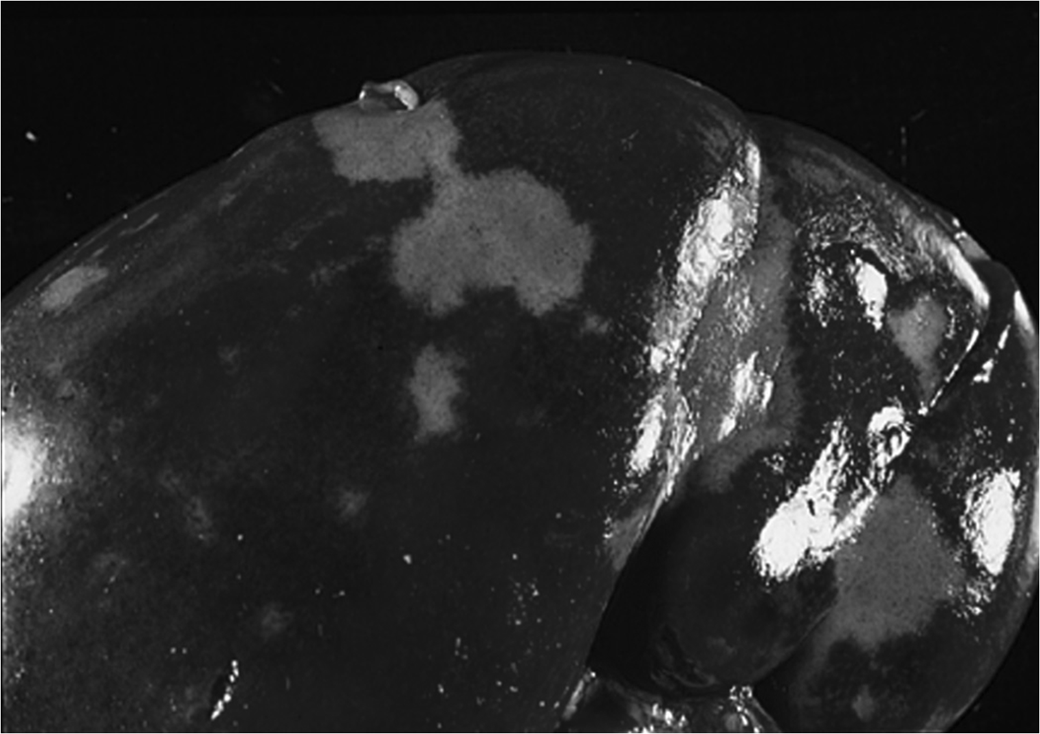

Chronic Passive Hyperemia of the Liver: In patients with right ventricular failure, the liver pathology is known as 'Nutmeg liver'. This characteristic appearance is due to multiple red, depressed cells resulting from prolonged congestion.

Red (hemorrhagic) infarct: Occurs in organs with dual blood supply (e.g., lung, small intestine), in venous occlusions, or in loose tissues where blood can collect in the infarcted area after necrosis. The dual supply and spongy nature of the lung allow blood to passively flow into the necrotic zone, making it hemorrhagic.